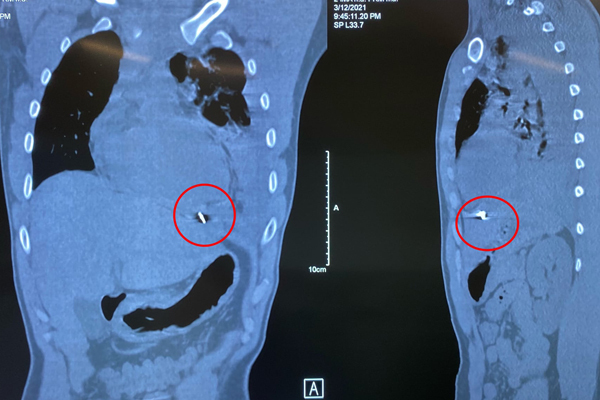

Bệnh nhân được thở oxy, theo dõi sát tình trạng hô hấp, đồng thời khảo sát bằng siêu âm và chụp CT lồng ngực, phát hiện tràn máu màng phổi trái mức độ nhiều, kèm xẹp phổi trái, có mảnh kim khí nằm trong cơ hoành, mặt dưới tâm thất trái.

Các bác sĩ thực hiện mở ngực đường bên vào khoang màng phổi trái, lấy ra dị vật là mảnh kim loại dài 1cm và gần 1,5 lít máu, máu đông rồi khâu lại cơ tim cầm máu, dẫn lưu màng tim, màng phổi trái.

Dị vật có cạnh sắc nhọn làm rách mặt trước màng tim và găm vào mặt hoành của màng tim, gây chảy máu dữ dội, tràn vào khoang màng phổi trái.